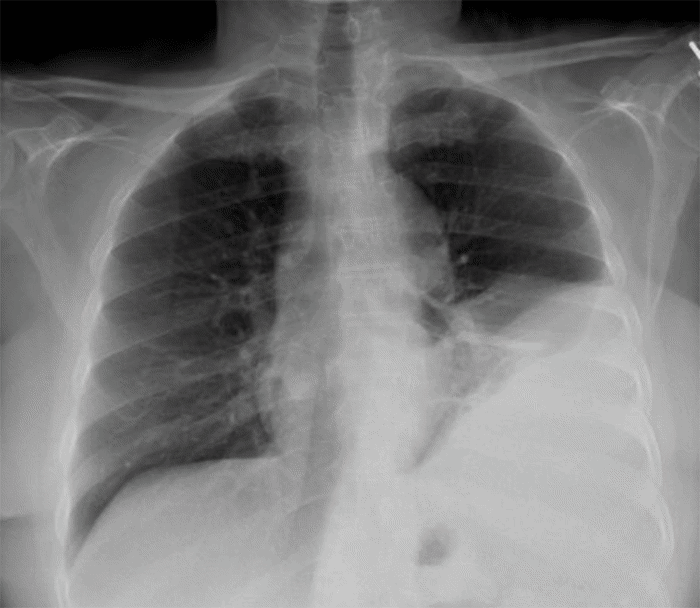

A 68-year-old female presented to our institution with abdominal pain, shortness of breath, and right-sided chest pain. A chest radiograph, obtained as part of a routine wellness visit, incidentally revealed a left-sided pleural effusion and ipsilateral atelectasis (Figure 1). At that time, the patient was asymptomatic, without shortness of breath, chest pain, cough, fever, or weight loss. A CT scan of the chest demonstrated a large, heterogeneous pleural effusion with internal septations, suggestive of loculation, and no evidence of masses or nodules within the lung parenchyma (Figure 2). The patient subsequently underwent ultrasound-guided thoracentesis, yielding only 30 mL of pleural fluid, which was sent for cytology, cell counts, cultures, and chemistry analysis. Pleural fluid analysis returned negative for malignancy, with benign mesothelial cells and chronic inflammatory cells.

Figure 2. Preoperative Computed Tomography of the Chest. Published with Permission

Preoperative CT of the chest demonstrating a large heterogeneous left pleural effusion with internal septations, suggestive of loculation